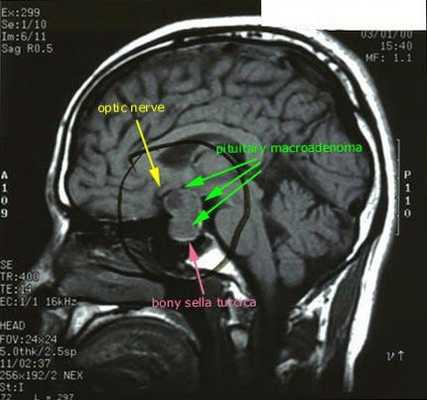

После подтверждённого гиперкортицизма необходимо проведение инструментальных методов исследования (МРТ гипофиза, КТ надпочечников).

При БИК в 80-85% случаев выявляют микроаденому гипофиза (опухоль до 10 мм), у остальных 15-20% — макроаденому (доброкачественное новообразование от 10 мм). [7]